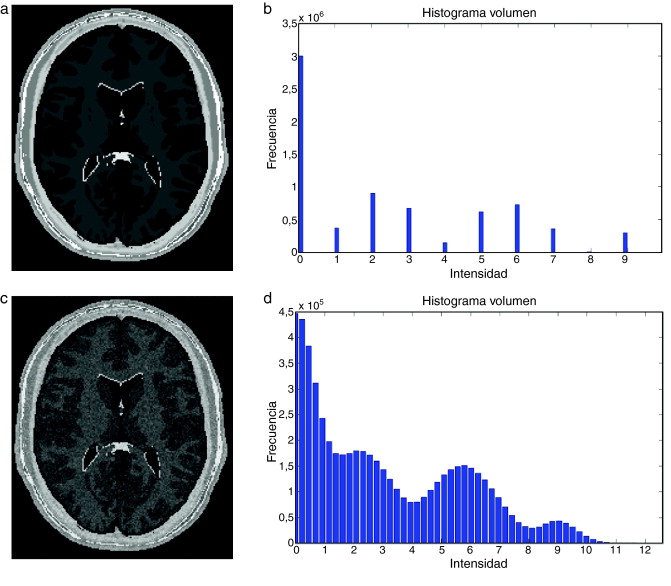

Para validar la funcionalidad y confiabilidad de la metodología propuesta fue necesario comparar nuestros modelos obtenidos con otros los modelos anatómicos proporcionados por otras fuentes a partir de las mismas imágenes médicas. Se utilizó el phantom del cerebro proporcionado por la base de datos libre BrainWeb[15] que simula IRM del cerebro a través de volúmenes «fuzzy», donde se representa de manera discreta cada clase de tejido: Materia Blanca (MB), Materia Gris (MG), Líquido Cefalorraquídeo (CSF), Grasa (G), etc. y volúmenes anatómicos discretos globales con cada clase conformada por voxels etiquetados con valores enteros (0 = Fondo, 1 = CSF, 2 = Materia Gris, 3 = Materia Blanca, 4 = Grasa, 5 = Músculo/Piel, 6 = Piel, 7 = Cráneo, 8 = Materia Glial, 9 = Tejido Conectivo).

El proceso de validación consistió en comparar dos volúmenes obtenidos a partir de IRM proporcionadas por esta base de datos: (a) un volumen segmentado de la zona de la materia blanca proporcionado por BrainWeb , y (b) el volumen de la materia blanca obtenido del phantom completo, empleando las rutinas de preprocesamiento y segmentación mencionadas a lo largo de este trabajo. Para ambos volúmenes, se calcularon el número total de pixels y los descriptores estadísticos descritos en la sección 2.6 (la media, desviación estándar, asimetría, homogeneidad y entropía). Calculándose finalmente el porcentaje de error absoluto de cada descriptor, entre los dos volúmenes evaluados.

Se aplicaron tres casos de validación, comparando el volumen de la zona de la materia blanca proporcionada por BrainWeb con: (a) El volumen de la zona de la materia blanca obtenida del phantom empleando la rutina de Region Growing . (b) El volumen obtenido empleando la rutina de Watershed. (c) El volumen obtenido con Region Growing aplicado al phantom corrompido con ruido gaussiano y filtrado con difusión anisotrópica. A continuación se describen los tres casos de validación aplicados.

4.1. Caso 1: segmentación Region Growing - BrainWeb

Con el interés de segmentar la zona de la materia blanca, se utilizó el algoritmo de Region Growing en el phantom discreto completo original. La zona segmentada fue comparada con la zona de la materia blanca proporcionada por BrainWeb . Para este fin, se empleó el análisis de texturas con el cálculo de descriptores estadísticos en ambos volúmenes y los respectivos porcentajes de error entre ambos. En la figura 24 se presenta los resultados obtenidos al segmentar la zona de la materia blanca en el volumen phantom con dimensiones de 181 × 217 × 181 (X × Y × Z ), con voxels isotrópicos de 1,0 mm3 , por visualización se presenta el corte axial 98. En la figura 24 .a se presenta la imagen phantom original, mostrando el corte número 98 del phantom . En la figura 24 .b se presenta la zona segmentada empleando el algoritmo Region Growing con seis seed points (semillas) elegidos de manera arbitraria sobre el área de la materia blanca, en forma de esferas volumétricas de 2 mm de radio, con el centro en las coordenadas X,Y,Z : Seed1= (66,59,98), Seed2 =(67,101,98), Seed3 =(60,158,98), Seed4 =(112,55,98), Seed5 =(113,103,98) y Seed6= (127,149,58). En la figura 24 .c se presenta la zona de la materia blanca proporcionada por BrainWeb.

|

|

|

Figura 24. Materia blanca segmentada en volumen phantom . (a) Corte axial número 98 de la imagen de phantom original. (b) Materia blanca segmentada con metodología propuesta empleando algoritmo Region Growing. (c) Zona de la materia blanca segmentada por BrainWeb . |

En la tabla 1 se presentan los valores estadísticos y los respectivos porcentajes de error, donde se puede observar que el porcentaje de error de las zonas segmentadas por Region Growing y la zona de la materia blanca proporcionada por BrainWeb no supera el 0,2487% para el caso del número global de pixels y el 0,2909% para los descriptores estadísticos.

4.2. Caso 2: segmentación Watershed - BrainWeb

Al igual que el caso anterior, el esquema de segmentación Watershed fue validado empleando el phantom de IRM del cerebro. En la figura 25 se presentan los resultados obtenidos al segmentar la zona de la materia blanca en el volumen phantom con dimensiones de 181 × 217 × 181 (X × Y × Z ), con voxels isotrópicos de 1,0 mm3 . En la figura 25 .a se presenta el corte número 98 de la imagen original. En la figura 25 .b se presenta la segmentación obtenida empleando el algoritmo de Watershed . En la figura 25 .c se presenta la zona de la materia blanca proporcionada por BrainWeb.

|

|

|

Figura 25. Materia blanca segmentada en volumen phantom de IRM del cerebro. (a) Corte axial 98 de imagen de phantom original. (b) Materia blanca segmentada con metodología propuesta empleando algoritmo Watershed. (c) Zona de la materia blanca segmentada por BrainWeb . |

Para validar los resultados, se empleó el análisis de texturas, calculando los descriptores estadísticos en los volúmenes obtenidos. En la tabla 2 se presentan los valores estadísticos y los respectivos porcentajes de error para ambos volúmenes. Obsérvese que el porcentaje de error del número global de pixels no supera el 1,2418%, y para los descriptores estadísticos no supera el 1,5201%.

4.3. Caso 3: filtrado de difusión anisotrópica y segmentación Region Growing - BrainWeb

En este caso, se corrompió el volumen phantom con ruido aditivo gaussiano y se procedió a aplicar las rutinas de filtrado y segmentación. Para suavizar el ruido de la imagen, se aplicó la rutina de filtrado con difusión anisotrópica (sección 2.2.1) y la segmentación de la zona de la materia blanca fue realizada con la rutina Region growing (sección 2.3.2). El flujograma de técnicas empleadas es similar al presentado en la figura 21 .

En la figura 27 se presentan los resultados obtenidos al segmentar la zona de la materia blanca con las rutinas y mencionadas. En la figura 27 .a se presenta la imagen phantom original, mostrando el corte axial número 98 del phantom . En la figura 27 .b se presenta la imagen phantom con ruido aditivo gaussiano. En la figura 27 .c es mostrada la imagen resultante luego de filtrar (b) con el filtro de difusión anisotrópica, además se observan las 5 semillas (seed points) seleccionadas de manera arbitraria sobre el área de la materia blanca. Las semillas empleadas tenían forma esférica de 2 pixels de radio, con el centro en las coordenadas X,Y,Z , las coordenadas de las semillas son: Seed1= (65,59,98), Seed2 =(112,55,98), Seed3 =(117,104,98), Seed4 =(127,137,98), Seed5 =(55,128,98). En la figura 27 .d se presenta el resultado de la segmentación (en rojo). En la figura 27 .e se presenta la zona de la materia blanca proporcionada por BrainWeb.

|

|

|

Figura 27. Materia blanca segmentada en volumen phantom . (a) Corte axial número 98 de imagen de phantom original. (b) Imagen original con ruido gaussiano agregado (c) Imagen con ruido filtrada con filtro de difusión anisotrópica. (d) Materia blanca segmentada con algoritmo Region Growing con 5 semillas esféricas. (e) Zona de la materia blanca segmentada por BrainWeb . |

Se calcularon los valores estadísticos y los respectivos porcentajes de error entre el volumen segmentado y el volumen proporcionado por BrainWeb, los resultados son presentados en la tabla 3 . Obsérvese que el porcentaje de error del número de pixels global no supera el 3,6374%, y para los descriptores estadísticos no supera el 7,1608%.

4.4. Caso 4: filtrado de difusión anisotrópica y segmentación Watershed - BrainWeb

En este caso, se utilizó el volumen phantom corrompido con ruido aditivo gaussiano, al cual se le aplicó la rutina de filtrado con difusión anisotrópica (sección 2.2.1) y la rutina de segmentación Region Growing (sección 2.3.2). El flujograma de técnicas empleadas es similar al presentado en la figura 14 .

En la figura 28 se presentan los resultados obtenidos al aplicar las rutinas mencionadas. En la figura 28 .a se presenta el corte 98 de la imagen de phantom original. En la figura 28 .b se presenta un corte de la imagen de phantom corrompida con ruido gaussiano . En la figura 28 .c se presenta la imagen filtrada con difusión anisotrópica. En la figura 28 .d se presenta la segmentación obtenida empleando la rutina Watershed . En la figura 28 .e se presenta la zona de la materia blanca proporciona por BrainWeb .

|

|

|